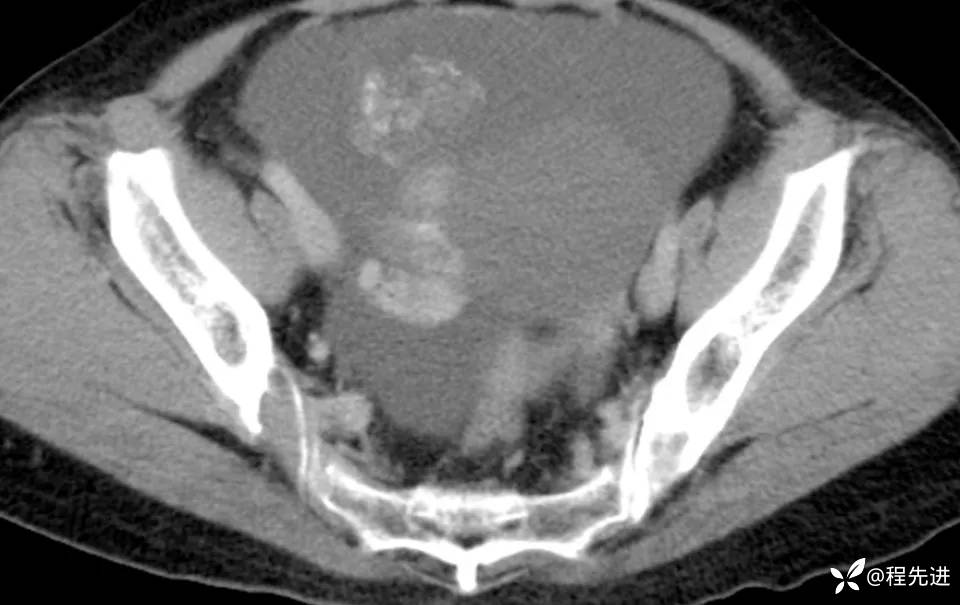

患者性别:女

患者年龄:56岁

简要病史:腹胀伴劳累性胸闷1月

肿标:CA125: 546.99U/ml;CA199: 269.9 U/ml,余未见异常

CT平扫+增强: